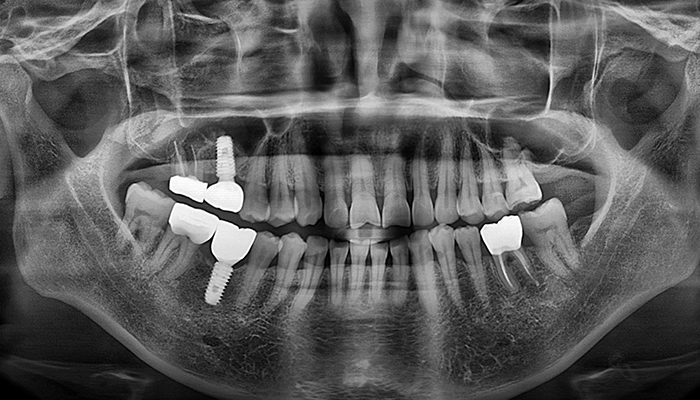

뼈이식 / 임플란트 식립공간 확보

잇몸을 절개하고 난 후 뼈를 넣고 상악동을 들어 올릴만한 작은 통로를 만들어 뼈이식할 공간과 임플란트 식립할 공간을 확보합니다.

잇몸 뼈이식 시술 진행

들어올린 빈 공간에 뼈를 이식하는데 이때 사용되는 뼈이식 재료로는 자가치아뼈, 자가골, 인공뼈, 합성골 등이 있습니다.

임플란트 매식체 식립

잔존하고 있는 잇몸뼈의 양에 따라 뼈이식과 동시에 임플란트 식립하기도 하고 6-9개월 후 식립하기도 합니다.